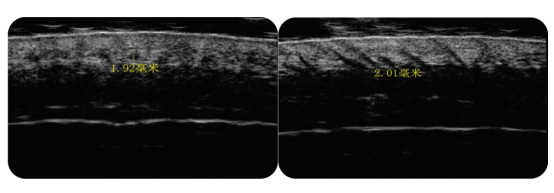

而肯波迪毛力塑直接选用独有的0.5MHZ频率,调节毛囊内组织细胞的信号及离子交换,强化毛囊干细胞和毛乳头细胞之间的信号传递,促进乳酸脱氢酶的活性化,从而提高毛囊干细胞、毛母质细胞的代谢活性,从而抑制毛囊退化,重塑毛囊动力。头皮的结构分为表皮层、真皮层及皮下组织,而负责生发的毛囊,就位于真皮层中。毛囊萎缩状态下,外在表现是掉发数量增加,而内在表现则是头皮真皮层变薄。头皮真皮层变薄,毛囊的生长环境变差,那长出来的头发能好到哪里去?

肯波迪毛力塑的热效应作用于头皮真皮深层组织,刺激胶原纤维即刻收缩,组织受热后产生一系列的理化效果,增强新陈代谢,使纤维细胞产生新的胶原纤维,促进萎缩毛囊真皮层胶原蛋白和弹性纤维的重组再生,增加头皮真皮层厚度,头皮恢复原有弹性,毛囊也得以拥有健康的生长环境。身体的各个器官运行都少不了血供,而头皮位于人体最高处,血液循环反重力而上,它的供养也会相对困难。头皮血供不足,毛囊微循环障碍,继而导致脱发。肯波迪毛力塑微热效应微循环,平衡细胞离子交换,修复细胞自然机能,增强头皮微循环及血管舒张、血液流动及氧气供给,加速不利产物代谢,促进头皮血液循环。头皮纤维化是头皮表皮层异常化,表现为头皮颜色暗沉、僵硬无弹性、紧绷发亮等现象,纤维化头皮处的毛干质地细软不健硕,无法支撑覆盖头皮。对于头皮纤维化,肯波迪毛力塑通过前面一系列的作用改善,效果层层递进,自内而外,由真皮层及表皮层,促进成纤维干细胞正常化及酶反应力,修复细胞自然机能促进细胞的增殖分化,预防并改善头皮纤维化;促进胶原蛋白及弹性纤维重组再生,头皮真皮增厚,恢复头皮弹性,延缓头皮衰老。